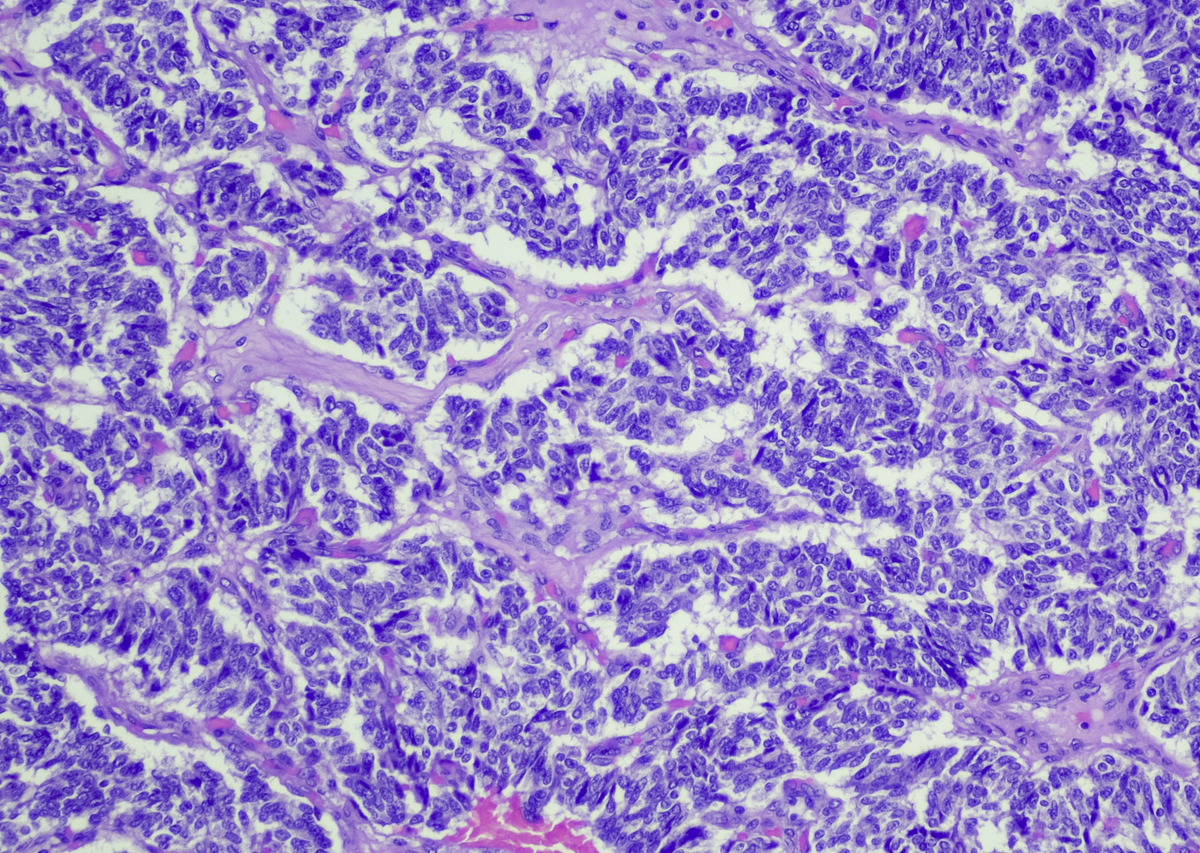

Νευροενδοκρινείς όγκοι στο πάγκρεας. iStock

Νευροενδοκρινείς όγκοι στο πάγκρεας.